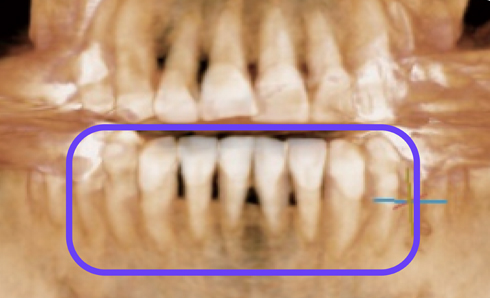

치석과 염증이 제거되며 스켈링 전보다 다소 잇몸이 내려가고 치간이 넓어진 느낌에 놀라실 수도 있습니다. 하지만 이는 치석과 염증이 있던 공간이 비워지고 잇몸이 원래의 잇몸뼈 부근으로 자리를 잡으며 생기는 변화입니다.

치석과 염증 등으로 잇몸과 잇몸뼈의 공간이 4mm가량이나 벌어져있던 치료 전과 비교했을 때 치료 후에는 잇몸과 잇몸뼈의 공간이 2~3mm를 유지할 수 있게 됩니다.